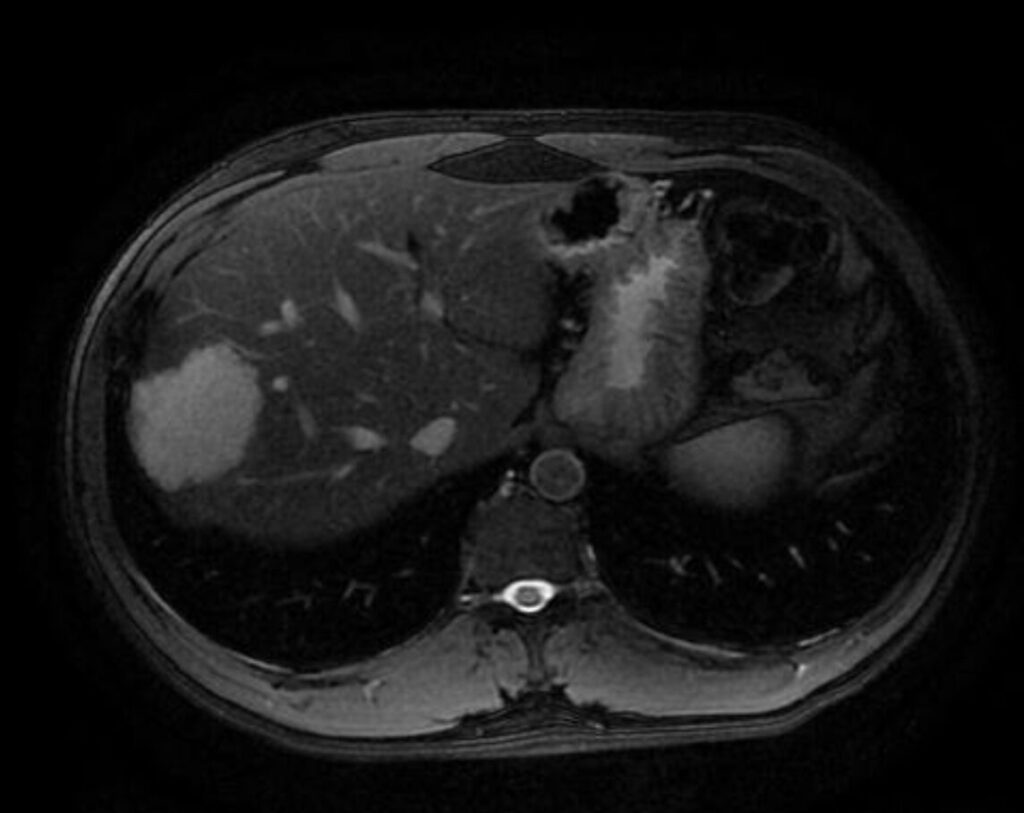

Aspetto RM

- Alterazione focale iso-ipointensa in T1, marcatamente iperintensa in T2, caratterizzata da un rapido e omogeneo enhancement in fase arteriosa senza wash-out, con ipointensità in fase epatospecifica.